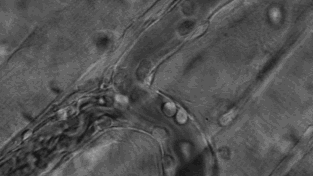

人体细胞总数在40~60万亿个之间,在这么多的细胞里,一些正常细胞由于物理、化学、病毒等致癌因子导致的原癌基因和抑癌基因突变后,就变成了癌细胞。一个正常人,每天会因各种原因产生6000个左右的癌细胞,而人体的免疫细胞则负责消灭癌细胞。美国细胞生物学会(ASCB)发布了一则微观大片,使用顶级的成像工具和技术,从免疫角度展示了人体中的一种免疫细胞T细胞杀死癌细胞的全过程。每个T细胞大约是人类头发直径的十分之一,它们在人体内不断巡逻,找出并杀死癌细胞或感染了危险病毒的细胞。当T细胞发现癌细胞时,通过分泌的毒素附着在癌细胞上,来检测、分辨正常细胞与癌细胞。查明之后,T细胞连接癌细胞,打破癌细胞外壁,向其表面引入毒性蛋白。一旦细胞毒素进入,癌细胞会逐渐衰弱、死亡。而T细胞继续在人体内巡逻,寻找下一个目标。其实除了上面提到的T细胞以外,身体里面还有很多免疫细胞在保护着我们,它们与癌细胞斗智斗勇,以抵御病毒保卫身体为终极目标。给大家分享几张免疫细胞“杀敌”的动图,来看看帅气的它们是如何英勇作战的:吞噬细胞在固有免疫中发挥重要作用,是清除致病微生物的重要免疫细胞。吞噬细胞包括两大类,即中性粒细胞(小吞噬细胞)及单核/巨噬细胞(大吞噬细胞)。两类吞噬细胞对入侵体内的微生物可极为快速的产生应答,尤以巨噬细胞的作用更为持久,是参与晚期固有免疫应答的主要效应细胞。NK细胞是T和B细胞并列的第三类淋巴细胞,不同于T、B细胞,它是具有直接杀伤靶细胞效应的一类淋巴细胞,靶细胞包括肿瘤细胞、病毒或细菌感染的细胞及机体某些正常细胞。NK细胞率先吹响战斗号角,以癌细胞头部为突破口发起进攻,癌细胞负隅顽抗NK细胞头部部队成功突破,大部队快速抵达战场,癌细胞瞬间瓦解NK细胞具有抗肿瘤、抗感染、免疫调节等功能,在病毒和寄生虫的抗感染免疫早期发挥重要作用。B细胞是体内产生抗体(免疫球蛋白)的细胞,B细胞也存在不同的亚群,主要执行体液免疫,也具有抗原提呈功能。通常情况下,人体的免疫系统可以高效地识别和消灭癌细胞,保证我们的身体健康。这些人体的天然“健康卫士”,绝对不会放过每一个逃逸的癌细胞。即便癌细胞成功逃逸进入血液,免疫细胞也会对癌细胞发起猛烈进攻。免疫细胞可穿过血管壁奔赴“战场”,向炎症和创伤组织进军、围剿。随着人类生命科学的不断发展,科学家们揭示了免疫细胞杀死癌细胞的作用机制,并证实了免疫细胞在对抗癌症上具有无可比拟的先天优势,根据这一特性,人类科学家探索出一系列通过补充T细胞、NK细胞、甚至使用CAR-T、CAR-NK等“大杀器”,来对抗癌症的免疫疗法。厉害了!我的免疫细胞!与病菌抗争的场面简直可以拍成一部精彩的战争电影了!想象一下,如果身体缺少它们每天顽强地抗敌的话,我们会怎样呢?应该连最基本的呼吸都难以做到了吧,毕竟空气中有那么多细菌,少了免疫细胞我们真没办法存活了......但是还是想跟大家说的一个真相是,免疫细胞虽然很强大,但是它们也会随着身体的老化而变得衰弱甚至死亡。因为少了免疫细胞的保护,身体对外来病毒的抵抗力就会变弱,人就会很容易生病。 |